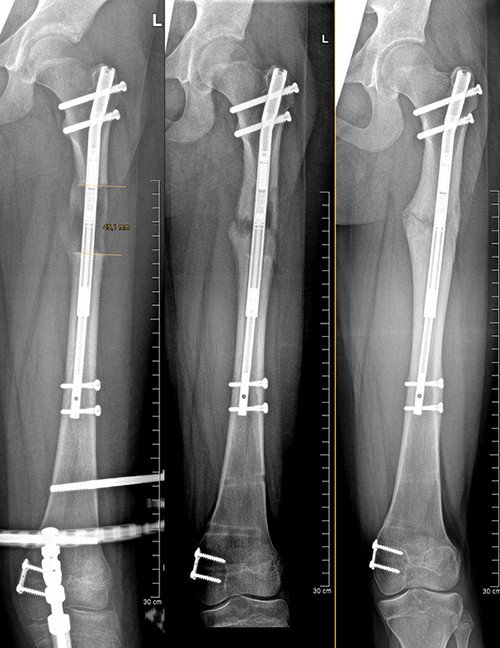

Dieses Beispiel zeigt eine bisher nicht beschriebene Kombination dieser Techniken. Bei diesem Mädchen besteht eine angeborene Längsfehlbildung des rechten Oberschenkels mit einer Differenz von 5 cm und eine X-Beinfehlstellung sowie auch eine Aussendrehung des Knochens. Zudem besteht eine beträchtliche Instabilität des Kniegelenkes aufgrund seit Geburt nicht vorhandener Kreuzbänder. Dies würde bei einer Verlängerung des Beines zu einer Luxation (Verrenkung) des Kniegelenkes führen können, die kaum behandelbar wäre.

Wir haben in dieser Situation daher den Oberschenkel mit dem Precice Nagel verlängert und gleichzeitig die Torsion korrigiert. Gleichzeitig haben wir aber auch das Knie mit einem Fixateur vor der Luxation geschützt und ein kleines Plättchen zur Wachstumslenkung an der Wachstumsfuge am Oberschenkel angebracht. So konnten die jeweiligen Vorteile der Verfahren perfekt genutzt werden, mit einem hervorragenden Resultat und grösstmöglichem Komfort für die Patientin.